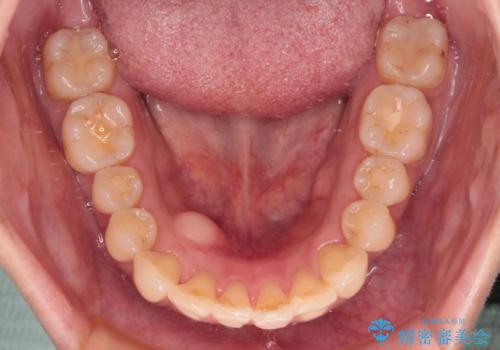

- 全体的なデコボコと、以前抜歯した歯のスペースを閉じた部分が気になるとのことで来院された患者様です。

左上第一大臼歯を抜歯した際に、スペースを閉じたそうですが、歯が傾斜してものが挟まって不快とのことでした。

インビザライン矯正で全体の歯列と整えるとともに、左上第一大臼歯部にはスペースを作り、インプラントによる補綴治療を行うこととしました。

歯の傾斜が改善され、インプラントによるクラウンが装着されたことで、物が挟まることもなくなりました。